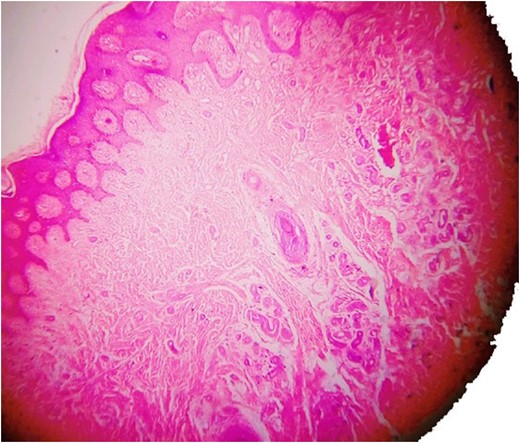

Another magnified section from showing thick walled capillaries.

Histopathology examination revealed grayish white to grayish brown lesions with hyperkeratitis of the epidermis and focally hyperplastic stratified squamous epithelium. Papillary dermis with numerous dilated, thin walled congested capillaries and the deep dermis with increased number of eccrine glands and numerous capillary channels intermingled with eccrine structure. The stroma was composed of fibrofatty tissue along with few pilar structures with the focal distribution of granulation tissue. Such a histological picture was found to be consistent with a diagnosis of EAKH.